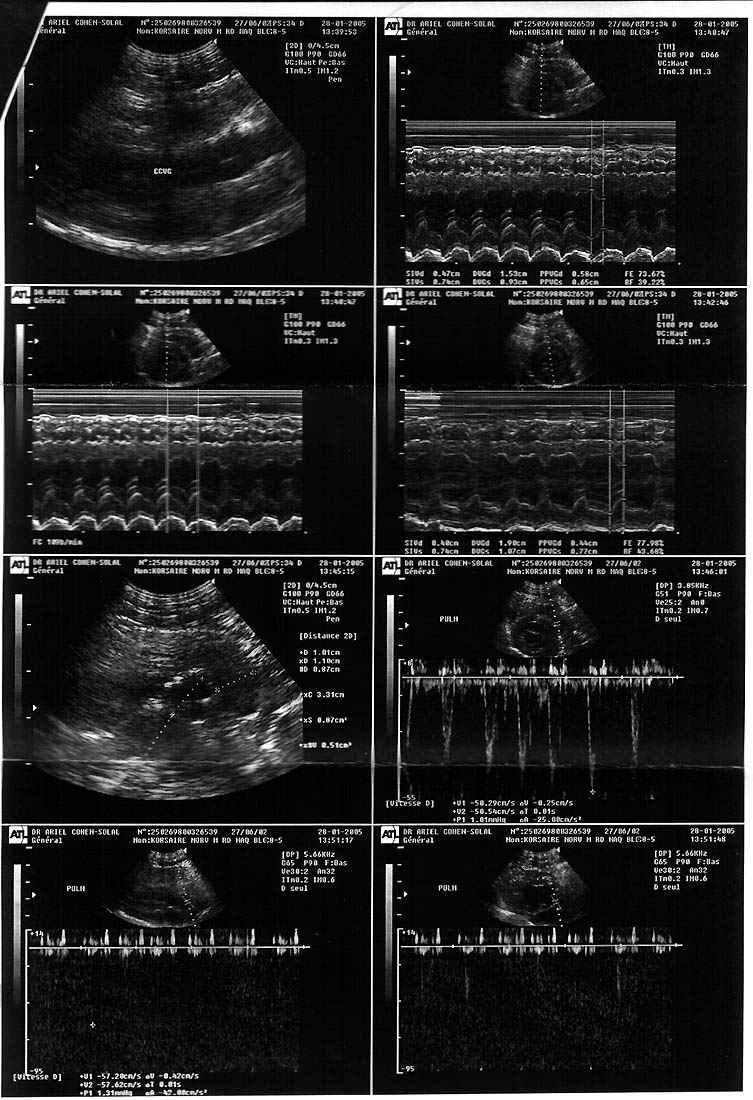

| Korsaire av Skara Brae*CH - (M) |

| EC Jericho av Skara Brae*CH EC/DM S*Moa's RH Gipsy Queen |

Sarah Runzis | 17/06/2002 | first premier |

none aucune |

normal | 2.5 years / ans |